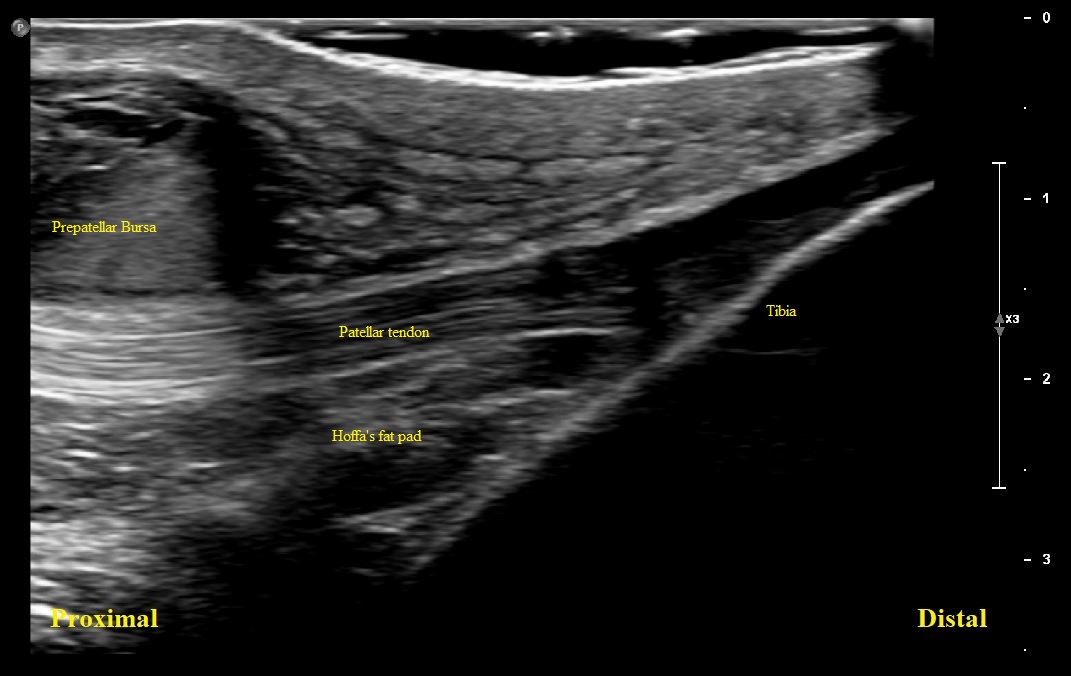

Long axis view of distal patellar tendon with overlying bursal distension

Long axis view of right distal patellar tendon. There is partial visualization of a distended prepatellar bursa with complex fluid. Distal Patellar tendon is intact. There is no superficial or deep infrapatellar bursal distension/bursitis

Long Axis view of Right Proximal Patellar tendon with large complex fluid within the prepatellar bursa with bursal lining hypertrophy. Patellar tendon is intact.